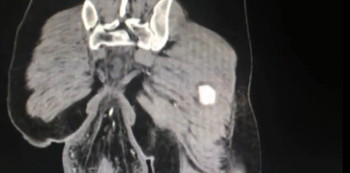

A CT scan revealed the 6.3-inch bulge hanging outside the patient’s anus, as well as blood spots and bruises along the patient’s intestinal wall.

• An x-ray, ultrasound, or CT scan may show problems with your child’s rectum. The healthcare provider may give contrast liquid to your child to help the intestines show up better in the pictures. Your healthcare provider may also place contrast liquid into your child’s anus. Tell the healthcare provider if your child has ever had an allergic reaction to contrast liquid.